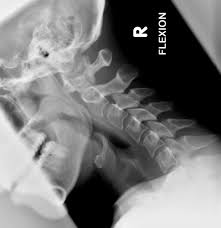

This procedure may be used to diagnose back or neck pain, fractures or broken bones, arthritis, degeneration of the disks, tumors, or other problems. Enter search terms and tap the search button. They show pictures of your internal tissues, bones, and organs. Please understand that our phone lines must be clear for urg. Here's what to expect with this painless procedure and why your dentist may recommend it.

This procedure may be used to diagnose back or neck pain, fractures or broken bones, arthritis, degeneration of the disks, tumors, or other problems. It's commonly done after someone has been in an automobile or other accident. They show pictures of your internal tissues, bones, and organs. Here's what to expect with this painless procedure and why your dentist may recommend it. Please understand that our phone lines must be clear for urg. Enter search terms and tap the search button.